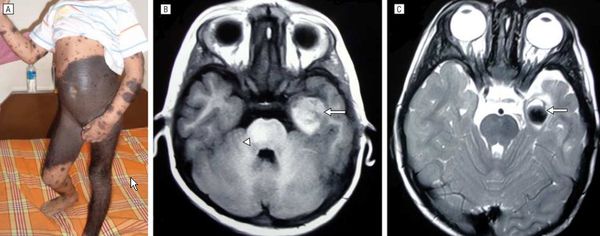

Нейрокожный меланоз

В редких случаях развивается нейрокожный меланоз — заболевание, при котором меланоциты разрастаются в центральной нервной системе. К таким нарушениям может приводить мутация гена BRAF [50] .

В исследовании американских учёных меланоз диагностировали у 26 из 379 пациентов с большими врождёнными невусами [12] . Заболевание может протекать без симптомов и случайно выявляться при МРТ, но в некоторых случаях оно сопровождается неврологическими нарушениями:

Неврологические симптомы могут развиться из-за кровоизлияния в желудочки головного мозга, нарушения циркуляции спинномозговой жидкости, сдавления спинного мозга или злокачественного перерождения меланоцитов [3] [14] .

МРТ головного и спинного мозга с контрастированием гадолинием обязательна для детей с высоким риском меланоза и неврологическими симптомами. В некоторых исследованиях при высоком риске меланоза рекомендовано делать МРТ в первые полгода жизни, даже если нет неврологических симптомов [15] .

Если большой невус расположен вдоль позвоночника или его окружают многочисленные невусы-спутники, МРТ проводят до четырёхмесячного возраста [35] .